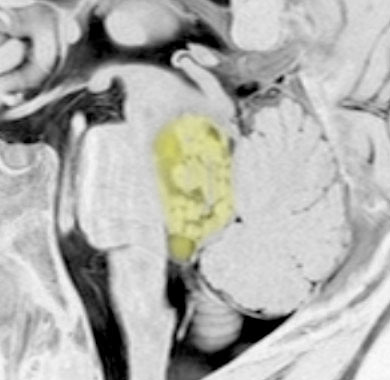

脊髄空洞症 syringomyeliaの合併

上と同じ患者さんです。大後頭孔での髄液流が悪くなるため,また腫瘍が何年もかかってゆっくり大きくなるので,脊髄に空洞ができました(脊髄空洞症)。脊髄の内部が裂けてしまうので,強い胸部の疼痛がでて発症しました。

第4脳室腫瘍を摘出するとこの空洞症は自然に治るので,何もしません。また症状も良くなることが多いです。

幼児の延髄に発生して第4脳室に伸展した毛様細胞性星細胞腫に合併した脊髄空洞症です。

ちなみにこれは毛様細胞性星細胞腫に合併する脊髄内のう胞ではありません。

この例の場合は,原因となった延髄腫瘍が摘出できないので,難治性の脊髄空洞症になります。